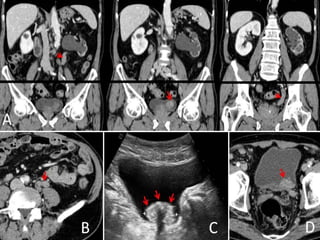

• #15 DISPLASIA UROTELIAL. Imágenes axiales de TCMD realizado en fase nefrográfica (A) y en fase excretora (B) que muestran la presencia de dos pequeñas proliferaciones papilares en la pared antero-superior de la vejiga urinaria (flechas y punta de flecha).

• #16 DISPLASIA UROTELIAL. A) Imagen axial e imagen coronal (B) por TC que muestran las pequeñas proliferaciones papilares. CARCINOMA UROTELIAL papilar con FENOTIPO PLASMOCITOIDE. La ecografía (A,B) muestra una ocupación de la luz vesical por una tumoración sólida de aspecto sésil.

• #17 METASTASIS GANGLIONAR DE CARCINOMA UROTELIAL. A) Imagen axial de TCMD que muestra importante componente adenopático ilíaco izquierdo con centro de aspecto necrótico y periferia hipervascular afectando parcialmente hueso ilíaco homolateral (punta de flecha en A). B) Adenopatía inguinal izquierda de similares características siendo todas ellas compatibles con afectación metastásica. C) Reconstrucción multiplanar coronal. Adenopatía inguinal izquierda referida previamente (asterisco).